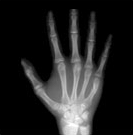

4) 같은 또래 아이들의 키보다 2표준편차 이상 작은 경우에는 성장클리닉 전문의의 진료가 필요합니다. 키가 정확히 또래 아이들보다 작은편인지 큰 편인지 진료를 통해 알아볼 수 있으며 성장판 촬영으로 골연령을 정확히 측정하는 것이 중요합니다.

| 열린경우 | 닫혀가는 경우 | 닫힌 경우 | |

| 경골 Tibia |

| 지골 Phalange |